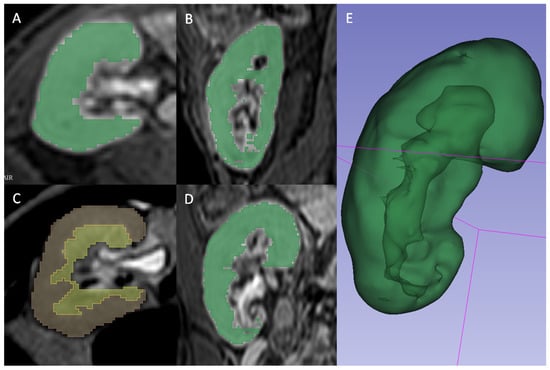

A radiologist (FM) blinded to the clinical outcomes segmented the transplanted kidneys using 3D Slicer software version 4.10.1 [18]. For T2 2D images, the manual contouring tool was used to select the whole parenchyma (Figure 2A), the medulla (Figure 2B), and the cortex (Figure 2C) obtained through previous segment subtraction. For T1 3D postcontrast images, the semiautomatic contouring tool based on intensity levels was used for the delineation of the whole parenchyma only since it was not possible to differentiate cortex and medulla reliably (Figure 2D). A different tool was adopted because, on T2-weighted sequences, the intensities of parenchyma and surrounding tissue were too similar to be reliably differentiated by the semiautomatic contouring tool. Moreover, the higher number of images of T1 3D sequences, caused by a lower thickness, made the manual contouring tool too slow to be adopted.

Figure 2. (A,B,D) Gradient Echo T1 weighted 3D venous-phase post-contrast sequence segmented in whole parenchyma by using the intensity-levels based semiautomatic contouring tool of 3D Slicer software, and depicted in axial view (A), sagittal view (B) and coronal view (D). (C) Single-shot T2 weighted sequences segmented with 3D Slicer software manual contouring tool, respectively subdivided in medulla (yellow) and cortex (red). (E) Three-dimensional rendering of whole parenchyma using T1 3D semiautomatic segmentation.